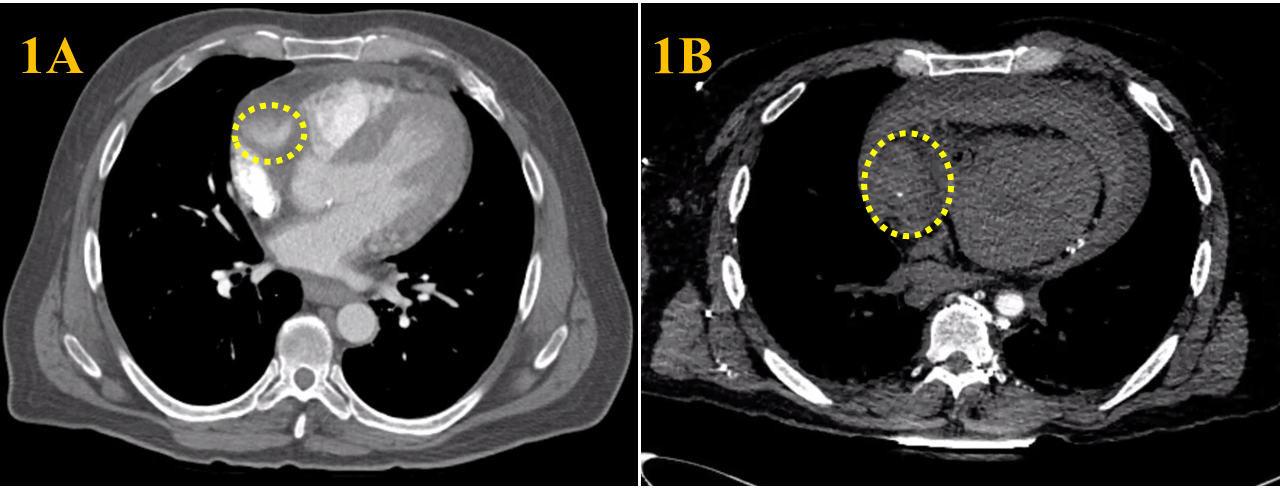

Imaging Findings: Initial CT of the chest found a 1.5x1.5 cm dilation of the proximal RCA (Fig1A). Post cardiac arrest, repeat CT of the chest revealed an interval increase of the proximal RCA measuring 3.5x3.5 cm and a moderate-to-large hemopericardium (Fig1B). An emergent limited TEE demonstrated a large circumferential hemopericardium and biventricular standstill.